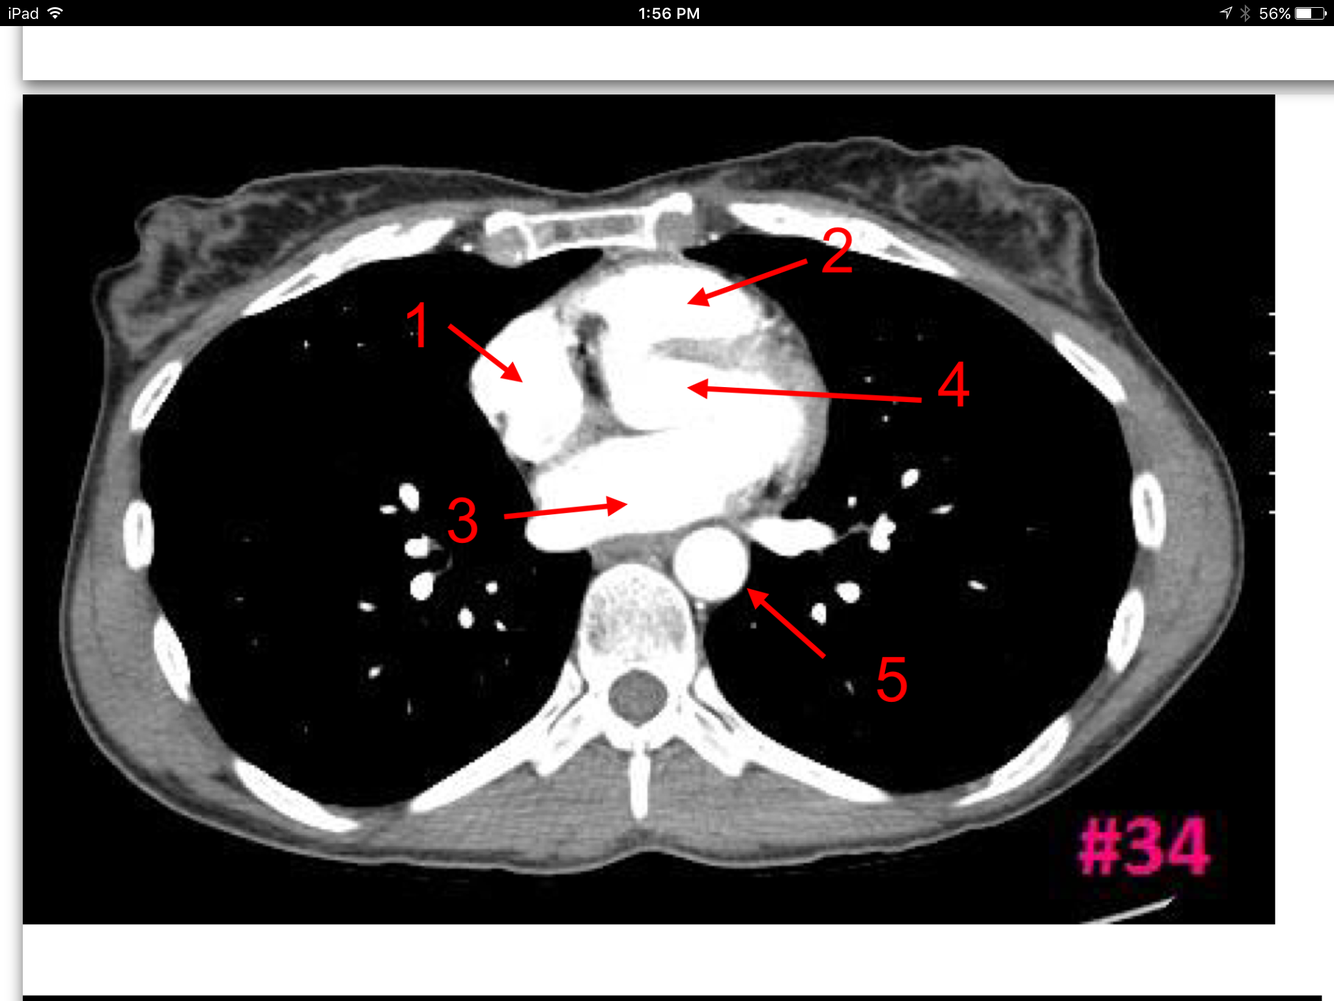

20

Q

Study These Flashcards

A

Rt atrium

Rt ventricle

Lt atrium

Lt ventricle

Thoracic aorta